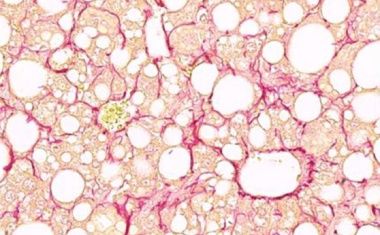

Die Leber spielt eine zentrale Rolle für die Energiespeicherung und -versorgung des Körpers. Bei Typ-2-Diabetes und MASLD (umgangssprachlich Fettleber) können die Mitochondrien nicht mehr effizient zwischen verschiedenen Energiequellen wechseln.